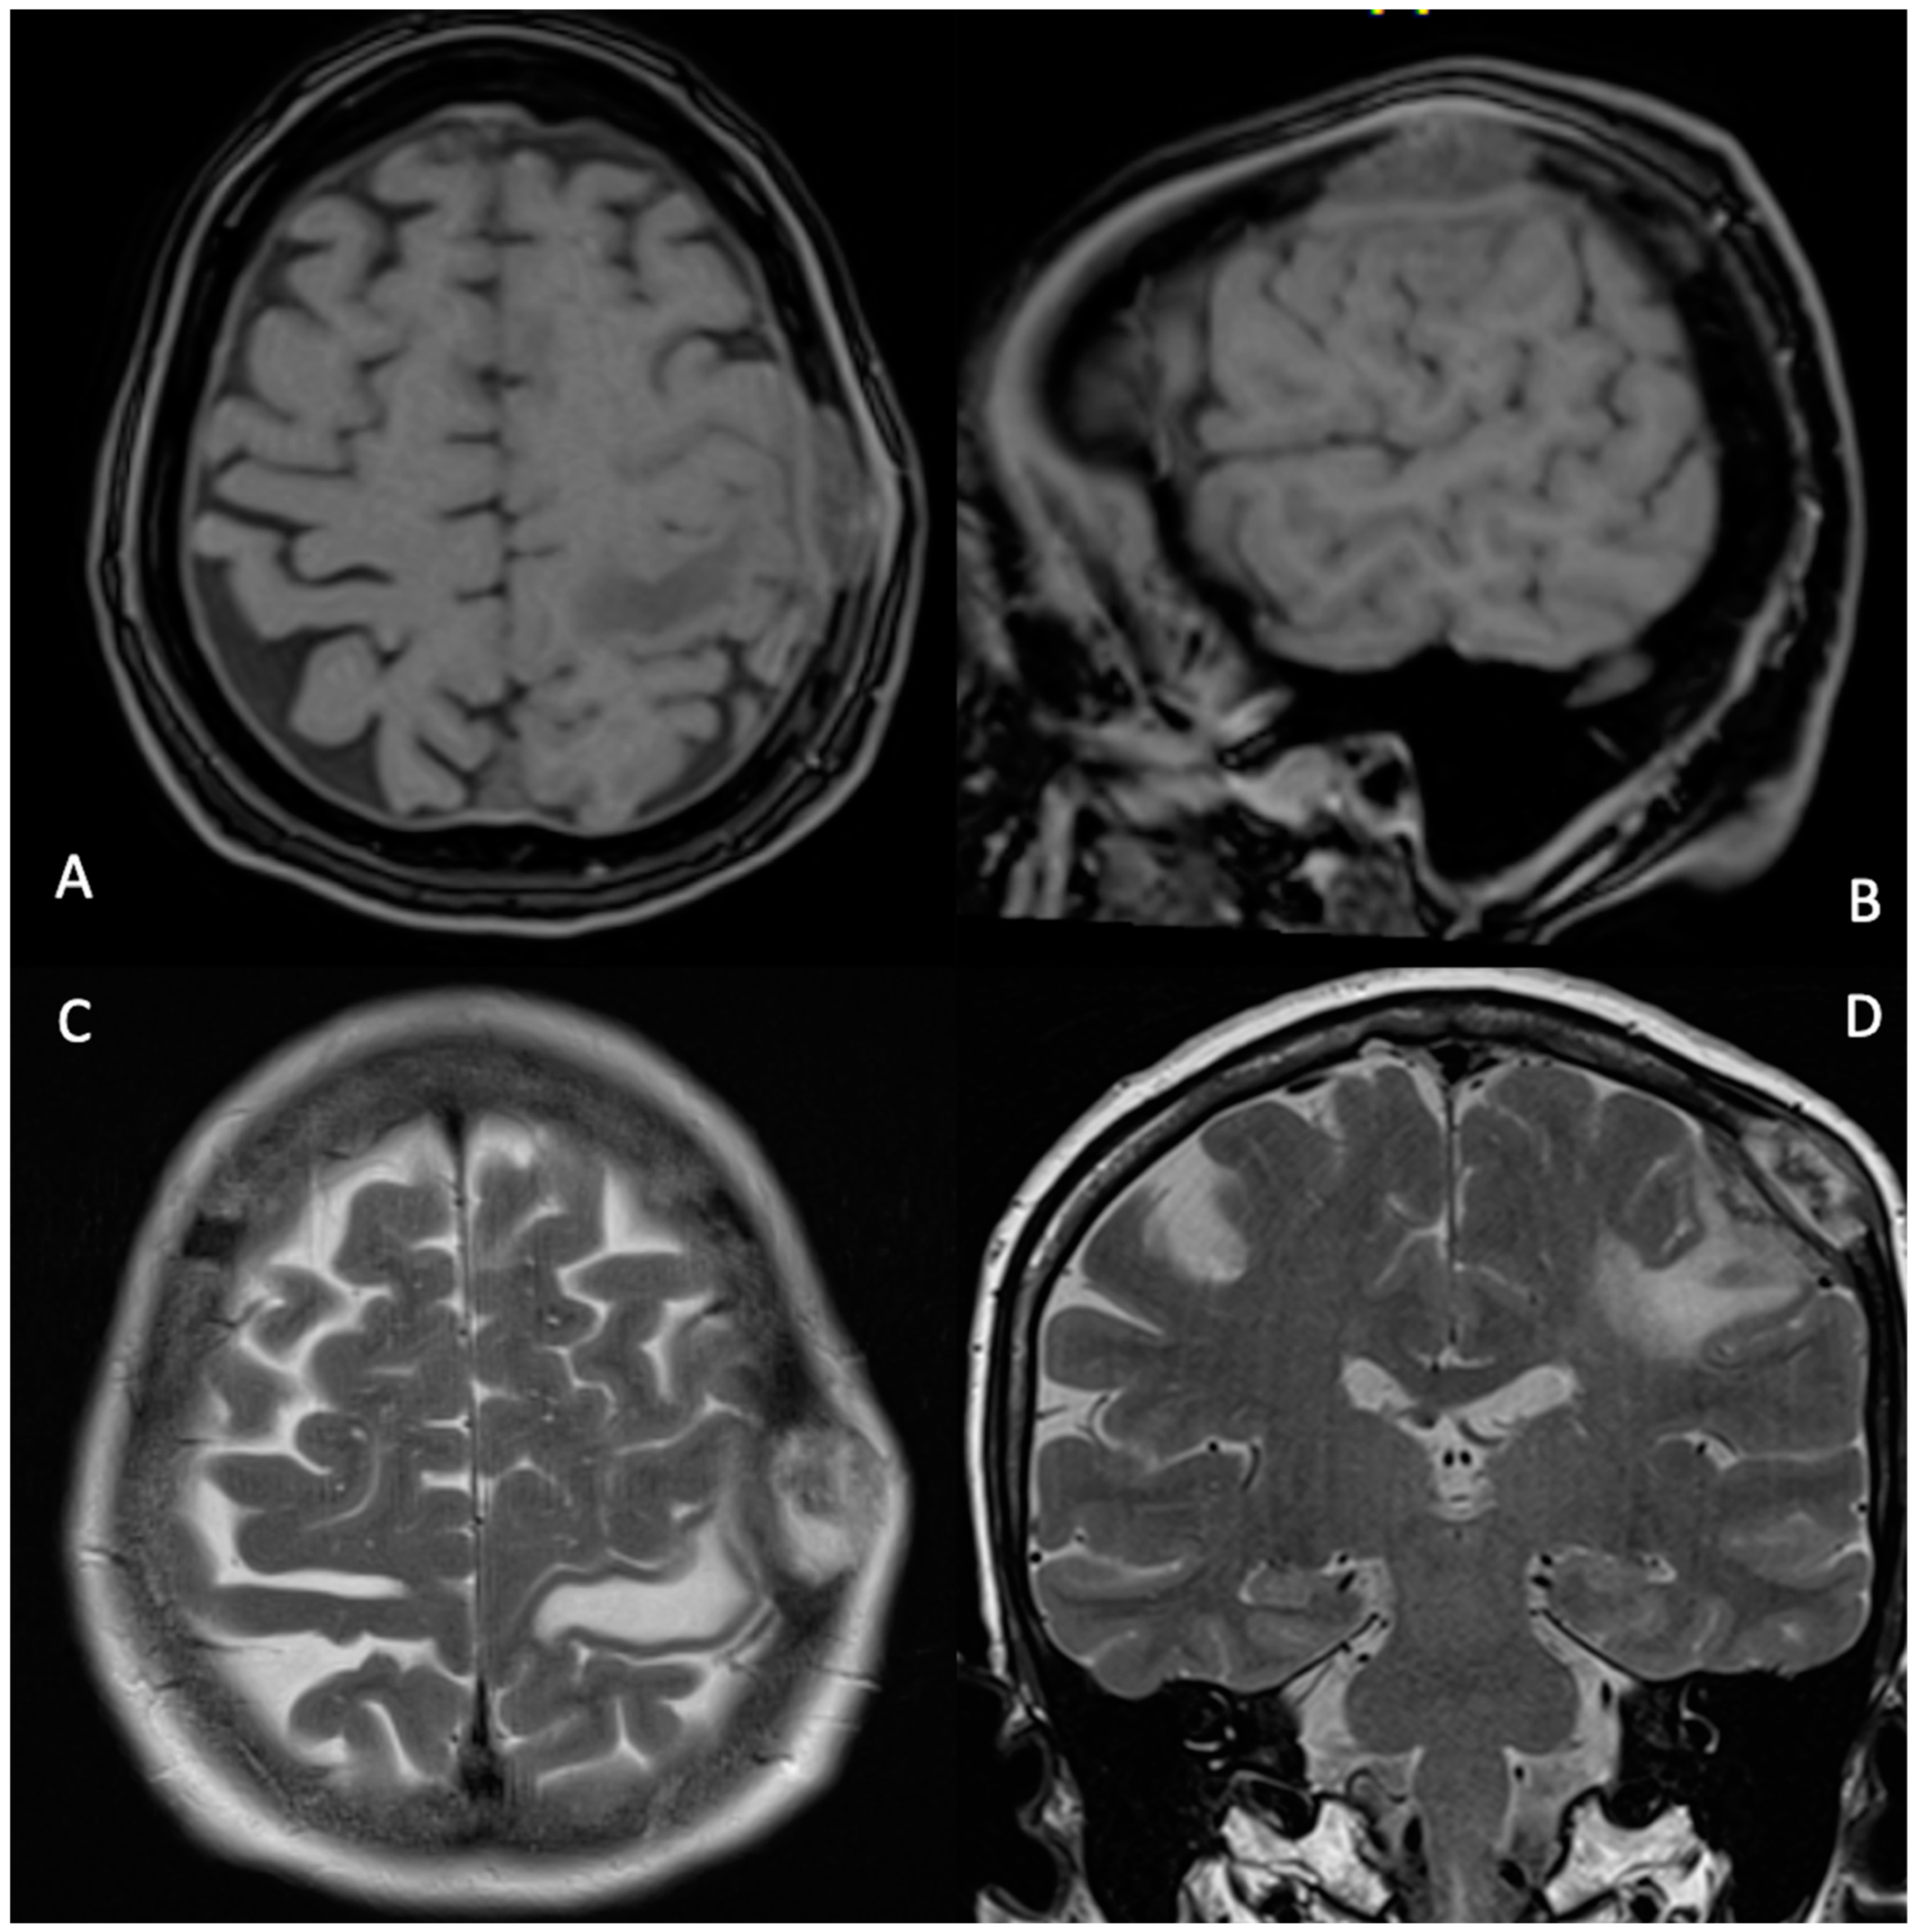

2. Case Description